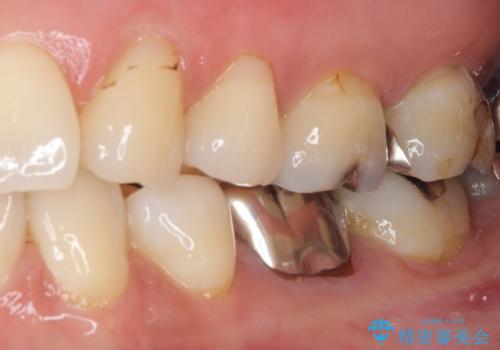

- 口を開けたときに目立ってしまう銀歯をセラミックに替えたいとのことで来院された患者様です。

上顎や親知らずにも銀歯がありましたが、今回の治療では目立つ下顎の銀歯4歯をセラミッククラウンやセラミックインレーに置き換えることにしました。